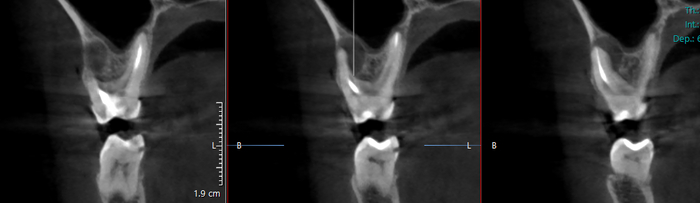

Я не стал делать 6ку сразу, т.к вообще не верил в результат (50\50 и 80\20 так себе прогнозы от докторов, я понимаю, что организм у всех разный, как и имунная система). прождав полгода, убедившись в результатах, накопив на 2 зуб, переболев гриппом иль ковидом выделил дни на лечение. Лечил в другой клинике, т.к предыдущий доктор ушёл, а эта ближе к дому. В прошлую среду лечение началось. Всё изначально пошло к херам, т.к после отхождения наркоза я почувствовал такой ад, что удаление зубов это так, цветочки, я удалял 4 зуба мудрости. Реально, внутри кисты и вокруг десны образовался маленький филиал ада, боль была чешуюся и одновременно будто нерв прищемили внутри лекарством, давление изнутри жуткое, всё начало гореть. начал изучать - пишут до 3 дней норм, ну окей, выпил кеторол, уснул т.к не спал почти сутки и в пятницу утром в 3, ровно через 1.5 часа после засыпания кеторол перестал действовать. локально воспалилась десна(без видимых признаков), жжение, боль, давление пошло на висок, в щёку и будто горячее что-то ходит по пазухе носа- к уху и так постоянно. выпил кеторол- не помог. В общем и целом до 20.10 с 17.10 я спал по 4-5 часов максимум, обычно 3 раза по 1 час- полтора, т.к просыпался от болей, не мог уснуть. в пятницу пошел к лору- думал что лекарство прорвалось в пазуху и поэтому так реакция. в эндоскоп лор не обнаружил жидкости, но обнаружил покраснений в носу, внутри пазухи. Почему я пошел к лору- гайморит пробился, правая ноздря, и нос так не дышал лет 15, я забыл что люди могут так дышать) 20.10 характер боли изменился, при давлении на зуб теперь не чувствую резкой боли, болит вокруг десны, район щеки. опухлость щеки не спадает с воскресенья, чувствуется температура вокруг зуба, при этом в воскресенье было 37, пнд и дальше уже нормальная. вчера не выдержал, пошел к зубному- принял другой врач, посмотрел без вскрытия, сообщил что у щеки очаг, мешочек, его либо вскрывать, либо ждать пока уйдет, гной типа не полностью образовался, надо резать десну возможно, зависит от опухлости и размера щеки в дальнейшем. т.е лекарство работает, боль изменилась, плановое вскрытие, чистка, замена кальцида на четверг назначена. сейчас вот поспал 5 часов, опять не могу, кеторол пью 6 день в перемешку с немисилом. Вчера назначили антибиотики, впыил вчера утром,боль проходит после болеутоляющего, но ноет потом весь день щека, пазуха, десна вокруг зуба и так уже 6 день. На снимке ниже кт месячной давности перед лечением, киста больше 6 мм, она в принципе очень выросла за полгода на милиметр-два точно

Есть вариант сделать кт перед вскрытием зуба у носовых пазух (по страховке от лора), есть вариант вскрыть мешочек выдавить гной и то что там есть, есть вариант надеяться, что отек спадет. В любом случае с болью 6 дней и бессонницей мне трудно соображать, зуб хотел вырвать уже раз 50. следующий плановый прием на промывку и смену кальцида назначен на 24.10. Останавливает от удаления цена импланта, прорезанное дыхание ноздри и то, что лекарство действует судя по всему, нет боли при жевании как раньше, правда вот ад у щеки\пазухи смущает.